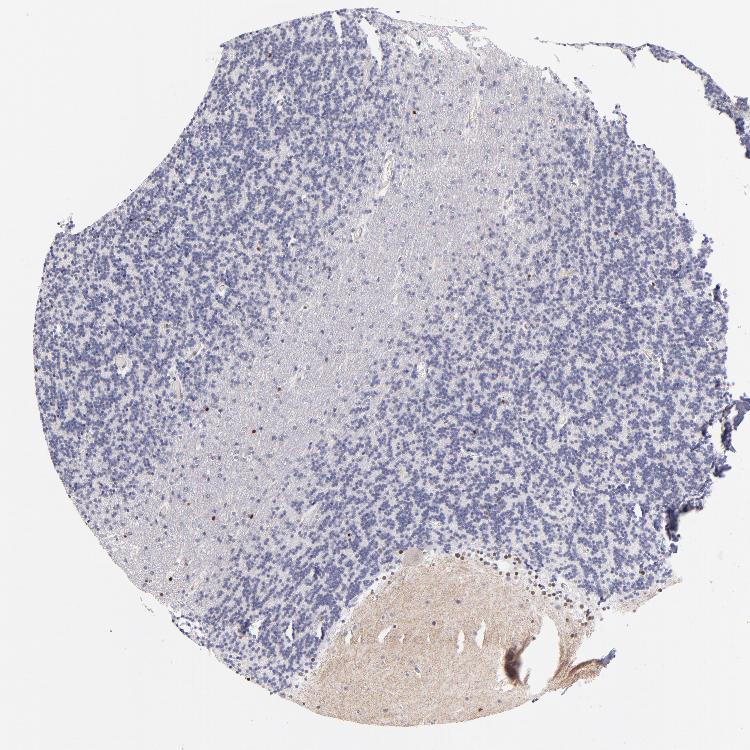

CEREBELLUM - Antibody stainingi

Antibody staining in the annotated cell types in the current human tissue is reported as not detected, low, medium, or high, based on conventional immunohistochemistry profiling in selected tissues. This score is based on the combination of the staining intensity and fraction of stained cells.

Each image is clickable and will lead to virtual microscopy that enables deeper exploration of all samples and also displays staining intensity scores, fraction scores and subcellular localization as well as patient and tissue information for each sample.

Antibody HPA001923Antibody HPA003908

Purkinje cells MediumNot detected

Cells in granular layer MediumLow

Cells in molecular layer MediumLow